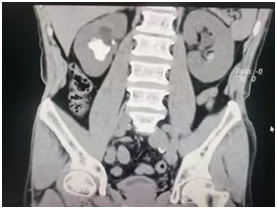

术后

输尿管鞘是什么名医动态|以柔克刚,无创取石——我院泌尿外科开展可弯曲负压吸引鞘+输尿管软镜钬激光碎石术_https://www.jmylbn.com_新闻资讯_第6张